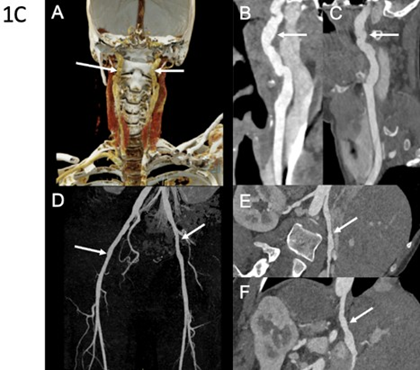

Third Case: A 31-year-old woman presented with splenic artery rupture complicated by hemorrhagic shock. Computed tomography angiography revealed multiple left renal infarctions associated with FMD-like renal artery stenosis, as well as numerous additional FMDlike arterial lesions (Table 1). These included irregularities of the cervical arteries, dissection and aneurysm of the right internal carotid artery, aneurysm of the right vertebral artery, aneurysmal dissections of the celiac trunk and hepatic artery, and irregular diameters of the iliac and external iliac arteries (Figure 1C). Clinical examination showed extensive spontaneous bruising, keloid scarring, alopecia, a suggestive facial appearance, small-joint hyperlaxity, and temporomandibular joint hypermobility. Molecular analysis identified a pathogenic splice-site variant in COL3A1. Family history revealed the premature death of her paternal grandmother due to arterial rupture at 27 years of age (Figure 2C).

Figure 1C: Arterial imaging of patient 3 on computed tomography angiography (CTA). CTA in a 40-year-old woman with diffuse vascular abnormalities. Coronal color-coded volume-rendered image (A) and curved planar reformations (B and C) show bilateral typical FMD-like lesions of the carotid arteries (arrows). Coronal 3D MIP image (D) demonstrates subtle vascular irregularities of the external iliac arteries (arrows). Curved planar reformations (E and F) show, respectively, multiple stenoses of the right renal artery and the celiac trunk. Molecular diagnosis of vascular EhlersDanlos syndrome was established after imaging.